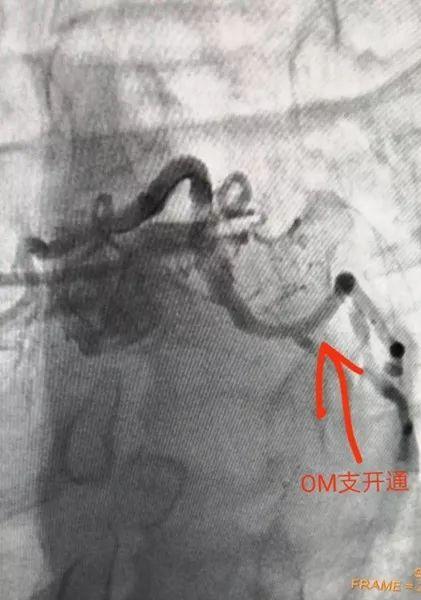

经过急查心肌酶谱明确急性心肌梗死的诊断,同时急诊的冠脉造影检查显示,这名年轻患者的前降支堵塞程度达到99%,血流缓慢,回旋支狭窄90%,立即给予介入支架术,术后患者症状消失。因为患者来医院较为及时,在接受了介入手术植入支架以后,病情很快缓解。

血管开通